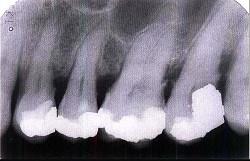

牙槽骨水平型吸收的特点是 ( )

A常形成骨上袋

B是最常见的吸收方式

C牙槽间隔

D牙槽嵴高度有明显降低

E以上均是